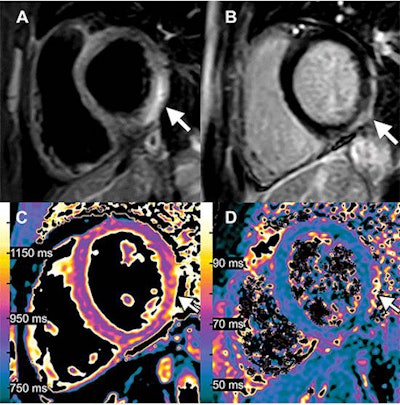

Images of a 38-year-old woman with Marfan syndrome who was diagnosed with intradural small bowel herniation through a torn right S1 dural ectasia. (A) Oblique global illumination rendering of abdominal CT scan after semiautomatic segmentation of the enlarged afferent small bowel (*). The hernia orifice (arrowheads) separates the peritoneal cavity and the intradural space. (B, C) T2-weighted MRI scans in (B) axial and (C) sagittal planes show the herniated loop (arrowheads in B) of small bowel (* in B) ascending at L5-S1 (arrows), causing significant compression of the adjacent cauda equina nerve roots. All figures courtesy of Radiology.The first runner-up is an article published on 3 August 2021, titled, "Myocarditis Following COVID-19 Vaccination," by a group at University Hospital Bonn, Germany. This is the third consecutive year in which a COVID-related image was honored among top contenders.

Images of a 15-year-old boy with myocarditis after COVID-19 vaccination. One day after receiving his second vaccination dose, he developed fever, myalgia, and intermittent tachycardia. (A) T2-weighted short inversion time inversion recovery MRI scan at 1.5 T in short-axis view shows focal high-signal intensities (arrow) at basal lateral and inferior wall, indicating myocardial edema. (B) Late gadolinium enhancement image in short-axis view shows corresponding linear subepicardial enhancement (arrow), indicating inflammatory myocardial necrosis. (C) T1 mapping and (D) T2 mapping in short-axis view show elevated T1 and T2 at the midventricular lateral and inferolateral wall (arrow in C and D), indicating acute myocardial injury (focal T1, 1165 msec; focal T2, 70 msec; institution-specific cutoff values for acute myocarditis: T1 global ≥1000 msec, T2 global ≥55.9 msec).The second runner-up was a tie between two articles. The first, "CT of Ongoing Intracerebral Hemorrhage," is by a group at the People's Hospital of Deyang City in Sichuan, China. The image captured the rapid evolution of a progressively expanding intracerebral hemorrhage in a 73-year-old man.